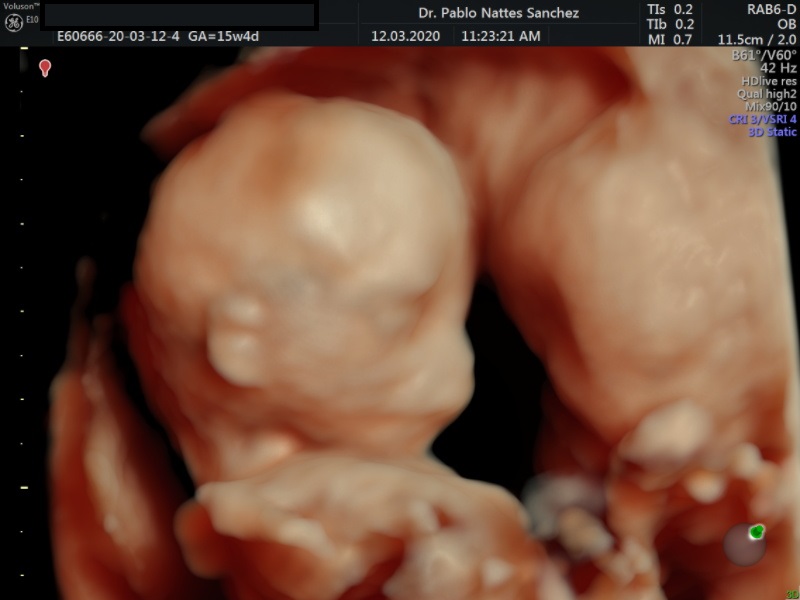

- Las Estructuras Anatómicas Fetales, diagnóstico precoz de Malformaciones (sensibilidad del 80%).